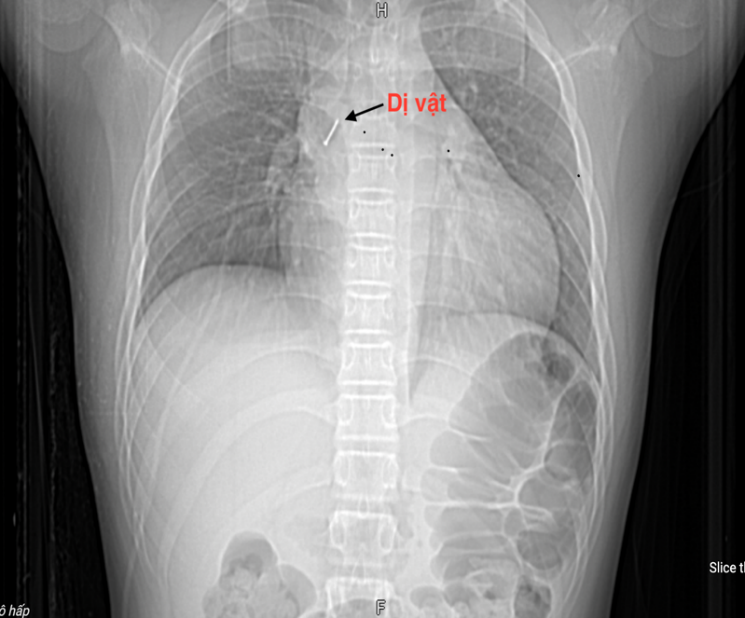

Familjen fick panik och tog barnet till ett närliggande sjukhus. Där genomgick patienten blodprover, datortomografi av bröstkorgen och flexibel bronkoskopi. Läkarna konstaterade att det främmande föremålet satt djupt inne i högra mellanbronken. Eftersom det främmande föremålet var vasst och penetrerade bronkväggen, vilket orsakade blödning och slemhinneödem, var det mycket svårt att avlägsna det. Efter mer än två timmars misslyckad operation förflyttades patienten akut till Centrala lungsjukhuset.

När de tog emot fallet utförde läkare, specialist II, doktor Nguyen Le Nhat Minh - chef för avdelningen för diagnostisk och interventionell endoskopi (Centrala lungsjukhuset) och hans team snabbt en flexibel bronkoskopiprocedur för att avlägsna det främmande föremålet för behandling.

"Det främmande föremålet är en vass nål som sitter fast i den mellanliggande bronken, vars vassa spets penetrerar djupt in i bronkväggen. Detta är ett mycket svårt fall att ta bort ett främmande föremål, eftersom patienten, utöver det främmande föremålets natur och egenskaper som ovan, också reagerar reflexmässigt, så det krävs snabb och absolut exakt manipulation för att undvika att riva sönder bronkväggen eller trycka det främmande föremålet djupare, vilket kan leda till infektion, blödning, pneumothorax och pneumomediastinum."

Dessa komplikationer kan till och med orsaka akut andningssvikt hos patienten. Därför, efter en omfattande bedömning, avlägsnade teamet försiktigt spikhuvudet som var inbäddat i bronkialväggen till ett fritt tillstånd med hjälp av specialiserade bronkoskopitänger, och avlägsnade sedan långsamt och framgångsrikt det främmande föremålet. Processen ägde rum inom 15 minuter, sa Dr. Minh.